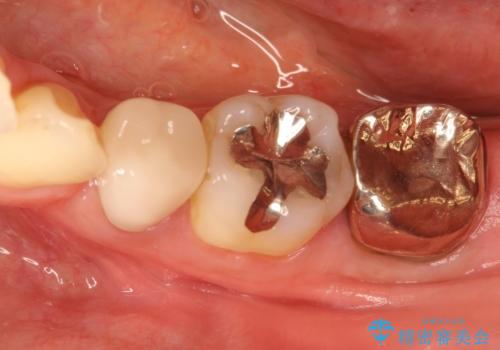

奥歯が痛い。根管治療からセラミッククラウン

- 奥歯が痛いことを主訴に来院されました。

レントゲンにて根尖病変を認め、根管治療を行ったのちセラミッククラウンにて修復しました。根管治療は川島先生に依頼。

咬合力が強くかかる部分には欠けるリスクのほとんどない金属を用いることが最良ですが審美性に劣ります。

今回は白い材料での修復を希望されたため、セラミッククラウンにて治療を行いました。